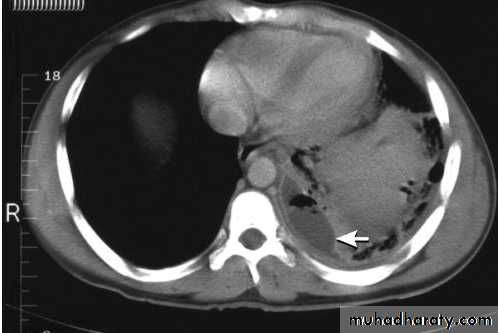

A computed tomography scan shows a posterior left pleural fluid collection (arrow) containing air (dark) and surrounded by thickened pleura.

The thickened pleura appears to be split by the lenticular fluid collection.